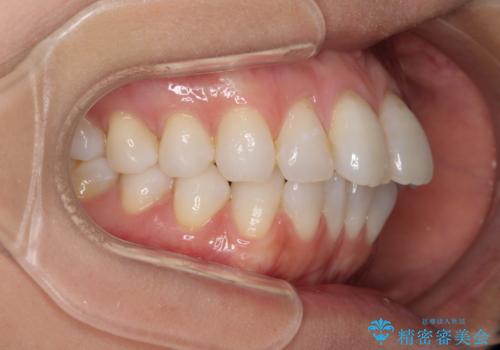

少しだけ飛び出た前歯を整えたい インビザラインによる矯正治療

- 少しだけ前に飛び出ている前歯を気にして来院された患者様です。

上顎歯列全体を後方に移動させる必要があり、インビザライン単体での治療は困難と判断し、補助装置により左右側方歯列を移動させた後にインビザラインを用いることとしました。

インビザライン単独でも上顎歯列全体を後方移動することで臼歯の咬み合わせを改善できる場合もあります。しかしながら、矯正治療は当初設定したゴールに到達する必要があり、今回のような場合ではインビザライン単独では達成の可能性が低くなるので、補助装置を使用して、より確実に治療を行うこととしています。